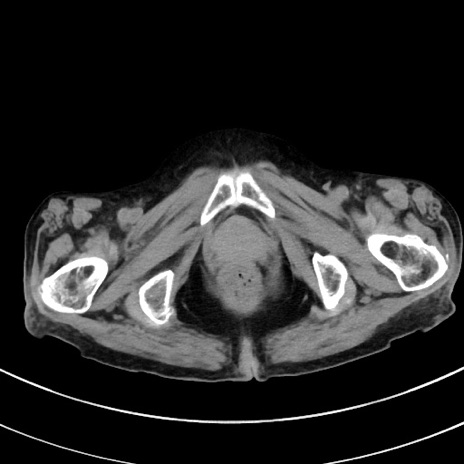

冠状断像

症例33(横断像)

【症例】70歳代 女性

【主訴】心窩部痛

【現病歴】延髄病変の精査・加療にて神経内科入院中。本日より心窩部痛あり。

【既往歴】虫垂炎

【身体所見】右下腹部を中心に圧痛と反跳痛あり。

【データ】WBC 10900、CRP 0.02